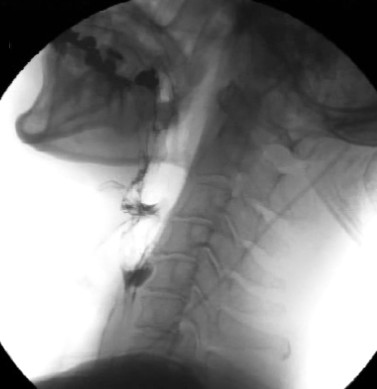

食道の上部にある輪状咽頭筋(cricopharyngeal muscle)の機能異常により、げっぷ困難を主症状とする病態です。輪状咽頭筋は、飲み込むときに弛緩して食物を食道に通し、げっぷ時には弛緩し胃内のエアーを食道から口腔に逆流させます。R-CPDでは輪状咽頭筋がうまく機能せず、げっぷが困難になります。食後に腹部膨満感、不快感、胸やけを伴うことが多く、炭酸水やビールを飲むと症状が悪化することがあります。吐き気があっても嘔吐できない、胸と首の下部から(カエルが鳴くような)ゴロゴロという音が聞こえることもあります。輪状咽頭筋にボツリヌス毒素(ボトックス)を注射して筋肉を弛緩させることで、げっぷ困難やその他の症状の改善が期待できます。R-CPDの診断やボツリヌス毒素注射の適応判断は、問診や嚥下造影検査などで総合的に行います。

食道の上部にある輪状咽頭筋は、嚥下運動中に舌骨上筋群の収縮とほぼ同期して弛緩します。この間に食べ物は咽頭から食道に運ばれます。脳卒中後などに輪状咽頭筋が過緊張状態に陥ると、輪状咽頭筋が弛緩しないまたは不完全になることがあります。このような嚥下障害に対して、輪状咽頭筋にボツリヌス毒素(ボトックス)を局所注入すると、数日後から徐々に輪状咽頭筋が弛緩し、食べ物の食道への通過改善は3~4ヶ月以上持続します。嚥下障害の中でも、咽頭収縮と喉頭挙上がある程度保たれている輪状咽頭筋弛緩障害例に対しては有効な治療法とされています(有効率74%)。輪状咽頭筋弛緩不全の診断やボツリヌス毒素注射の適応判断は、問診や嚥下造影検査などで総合的に行います。